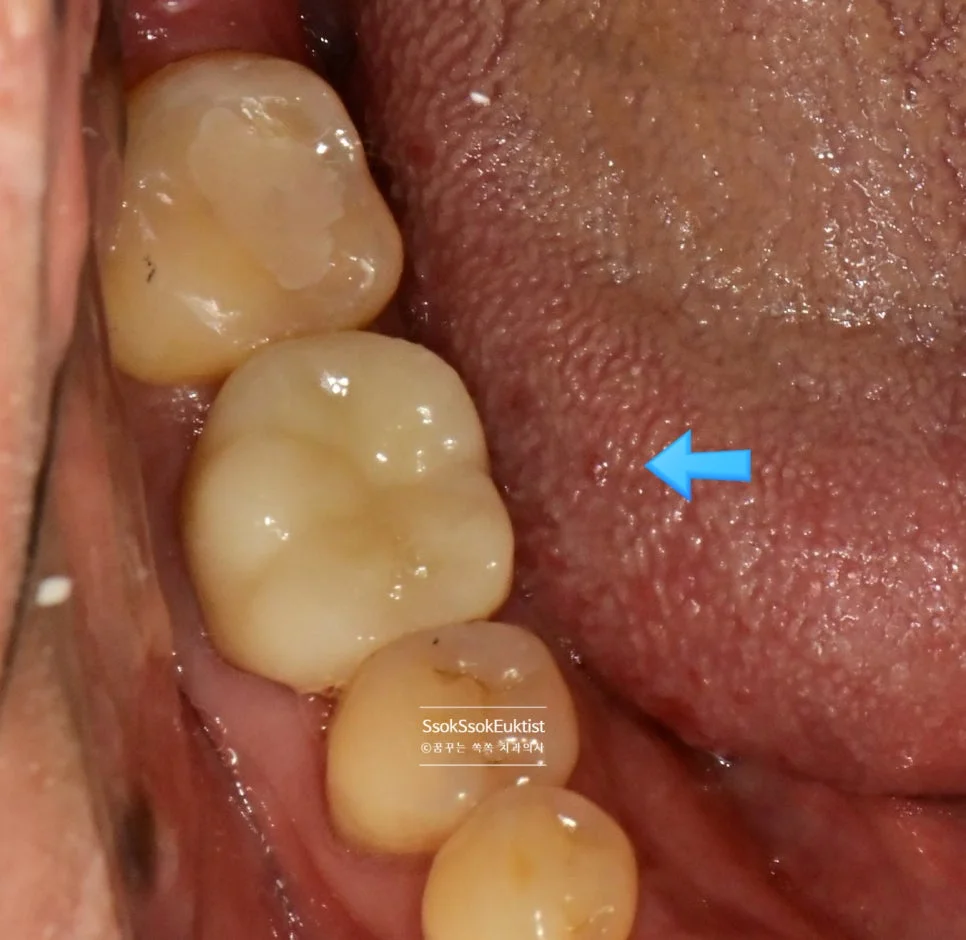

치아가 시린 증상이 심하여 신경치료를 원하시고 실제 필요한 상황입니다.

강서구 치과 서울쏙쏙치과에서 신경치료의 핵심 세 가지 알려드릴게요^^